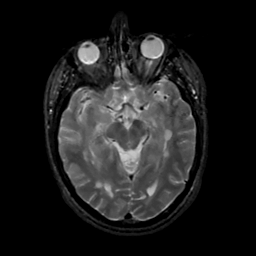

MR Study #15, June 9, 1991 -- Slice #21